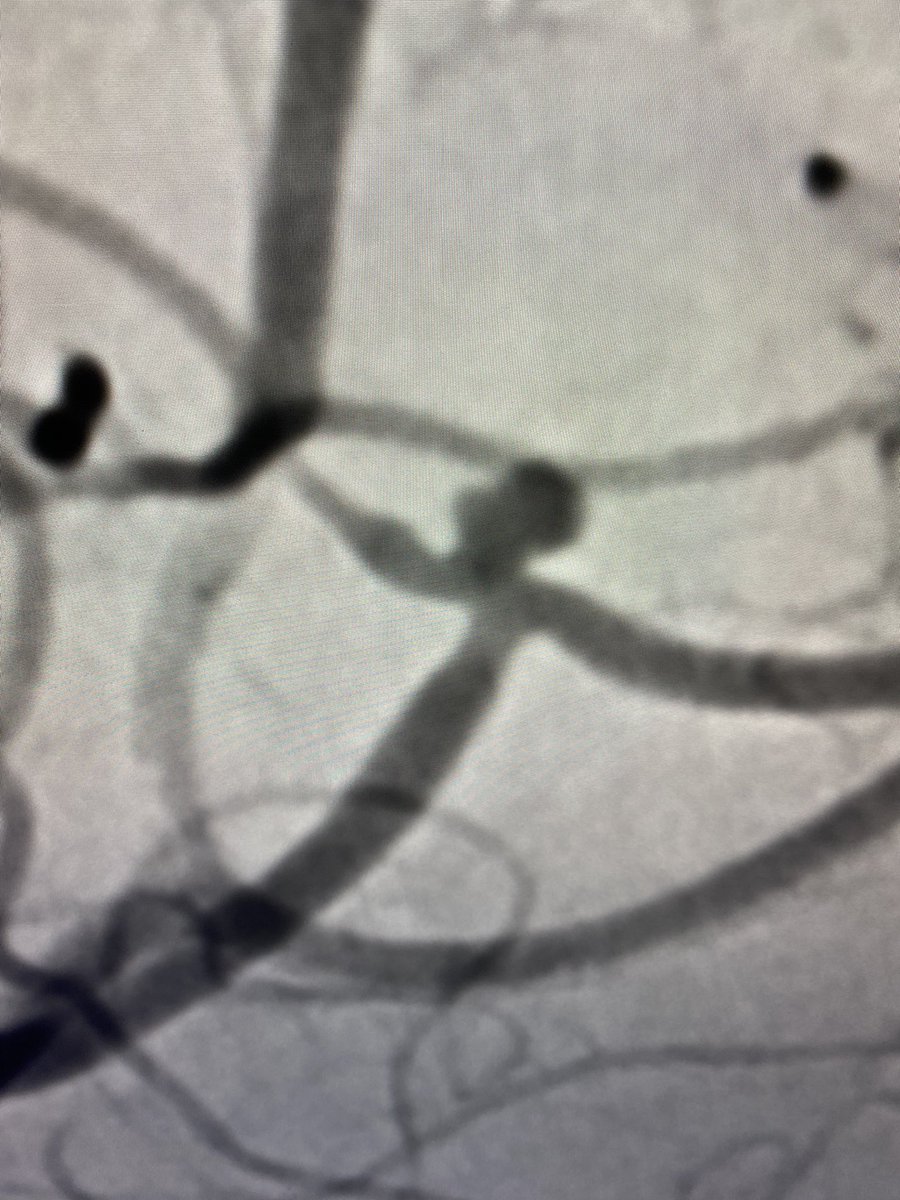

Please check out our new classification system for shunting AV lesions of the spine! We emphasis lesions with high risk features as these cause stroke and hemorrhage. A big thank you to @UCSF_NIR , @UCSFimaging , and @JNIS_BMJ.

Arteriovenous shunts of the cervical spine: patient demographics, presentation, patterns of high-risk venous drainage, and updated classification jnis.bmj.com/content/early/…